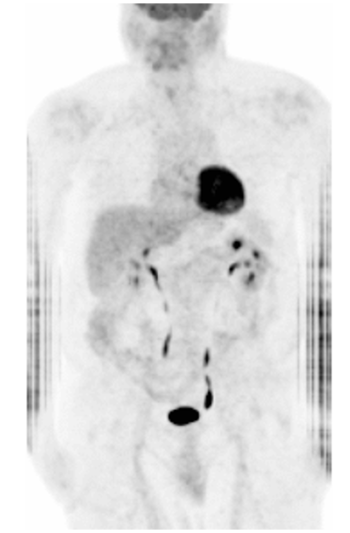

IV.4.7.2. Miről alkot képet a PET?

Agyműködés vizsgálata: epilepszia, Alzheimer-kór, agytumorok.

Onkológia: tumorok és áttétek pontos lokalizációja.

Kardiológia: a szívizom működésének, helyreállásának vizsgálata.

Kutatási cél: neuropszichológiai és farmakológiai kutatások.